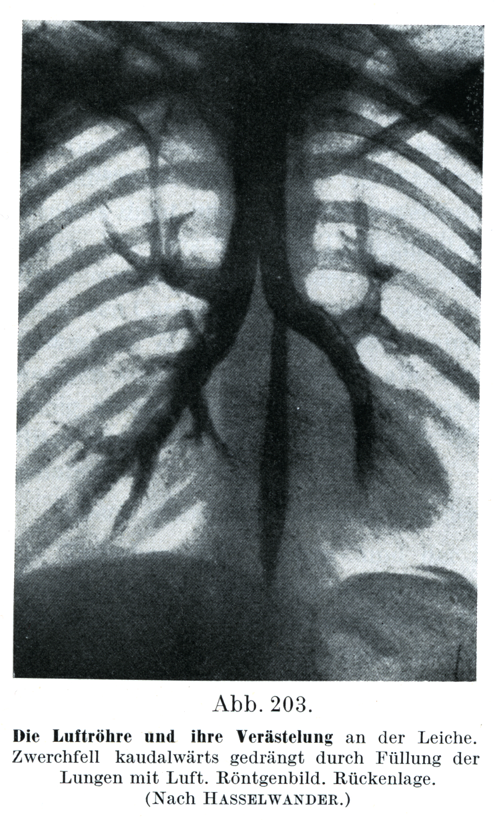

[図203]気管とその分枝(死体)

横隔膜は塑気で充された肺によって下方に押しやられている.レントゲン写真.背位(Haßelwanderによる)